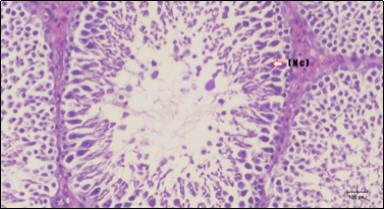

Histological examination of control rats' testis showed normal histological structure of the seminiferous tubules with an increase in the spermatogonia and other spermatocytes compared with the diabetic rats which showed an obvious decrease in the count of germinal cells generally and sloughing of germ cell in the lumen of seminiferous tubules in addition to absence of the mature sperms (Figure 3 and Figure 4). Rats tested of Fenugreek group and those treated with Glimepiride (Figure 5 and Figure 6) presented an increase in the number of spermatogenic cells and mature sperms with few focal necrotic cells. Whereas the combination therapy group showed normal histological structure of the seminiferous tubules with normal spermatogonia, presence of ledying cells and more mature of sperms (Figure 7). STZ reduced testosterone production, suggesting a decrease in the function of both Leydig (testosterone producing cell) and Sertoli (spermatogenesis) cells, which might be caused by a reduction in insulin secretion. These changes are probably due to increased Reactive Oxygen Species (ROS) production by accelerated Advanced Glycation End Products (AGE) formation 31 hexosamine and Protein Kinase C pathway. The administration of Fenugreek seeds to diabetic rats significantly decrease of sperm shape abnormality and improve the sperm count 32. Glimepiride reduced sperm abnormality and increased testis weights and sperm count by its antioxidant action 30. The potential protective efficacy of Fenugreek seed extract when added to Glimepiride was observed on reproductive systems.

Figure 6.Photomicrogragh of testis section of treated rat showing increased number of spermatogenic cells from spermatogonia till spermatozoa (star). Few liquid infiltration in wide interstitial tissue (H&E) (40X).